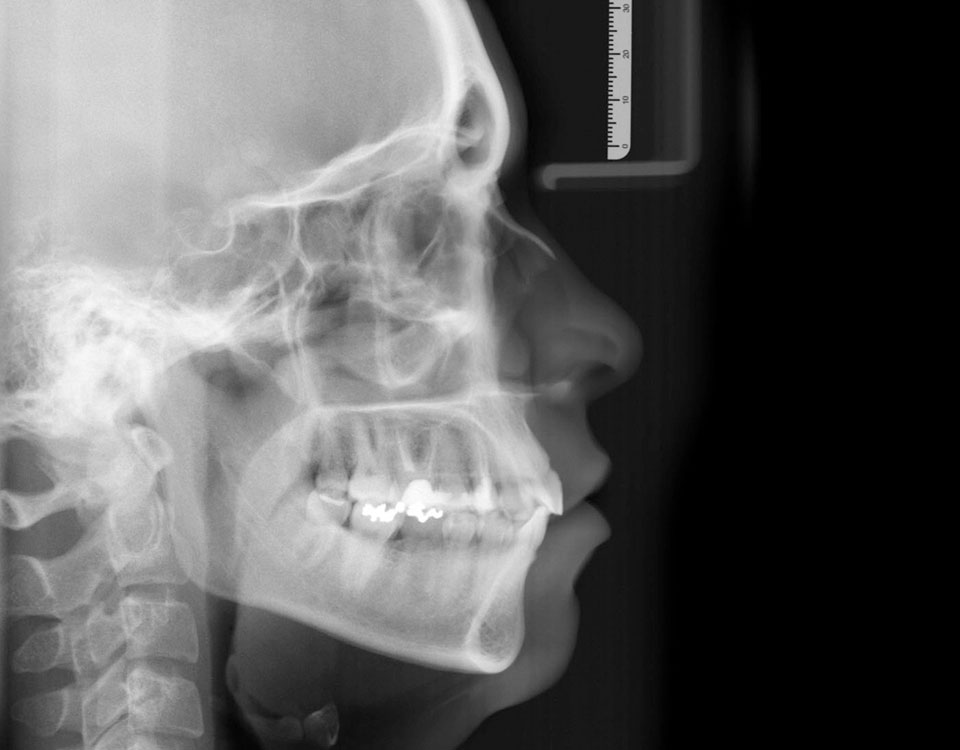

Telerradiografia

A Telerradiografia é uma técnica que auxilia os Médicos Dentistas a examinar o osso subjacente, as raízes dos dentes ou dentes não irrompidos, assim como as áreas de contato entre os dentes. Muito útil no plano de tratamento de ortodontia.